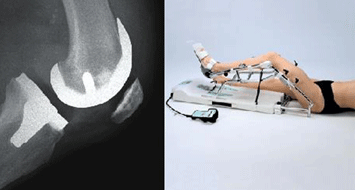

Ky operacion konsiston në rikostruksionin e sipërfaqes së kockave të gjurit me vendosjen e një proteze, e cila, ashtu si gjuri normal ka sipërfaqe të lëmuara dhe është në gjendje të përballojë peshimin ne toke.

Periudha pas operacionit: Në ditët pas operacionit ka gjithmonë një ngritje të temperaturës e ndonjëherë arrin edhe mbi 38°, gjë që është e lidhur me procesin inflamator të operacionit. Kjo temperaturë mund të vazhdojë për disa ditë. Ditën e dytë pas operacionit, do të hiqen drenazhet e vendosura brenda gjurit. Nga ky moment mund të fillohet gjimnastika pasive e gjurit me anë të një makine të posaçme (kinetek).